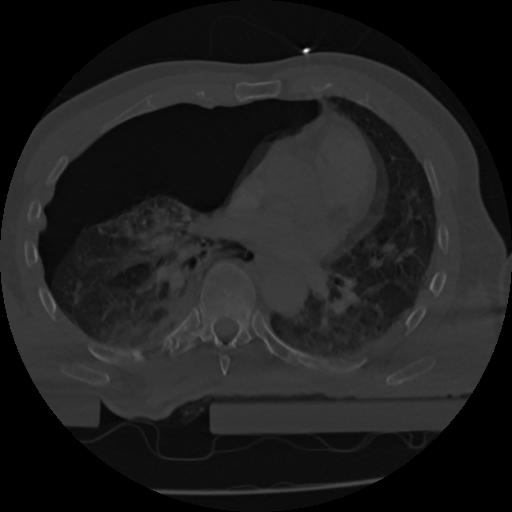

22 ANGIO,CE,Vol,0.5,ANGIO,,